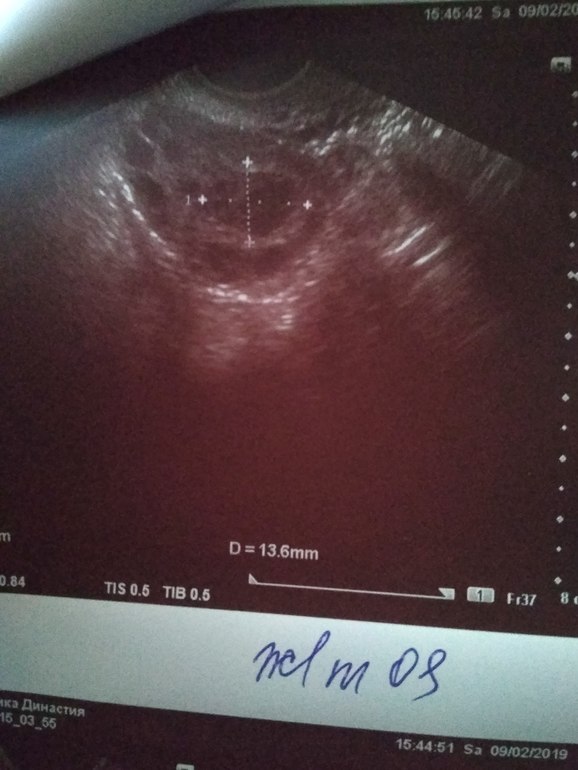

9.02.19 18 ДЦ - 36,6 ( в этот день не выдержала пошла на фолликулометрию...,там мне сказали,что овуляция у меня была...когда непонятно...делала тесты на овуляцию 2 полоска была призрачная...делала тесты с 4.02.19 по 8.02.19 как положено по инструкции. По фолликулометрии вот что сказали: Эндометрий 5 мм однородный,повышенной эхогенности..., в левом яичнике кистозное желтое тело 18*14 мм со слабым кровотоком по периферии (врач узист сказал,что в желтом теле есть немного крови...я ее спросила почему так?? Она толком не ответила,сказала типа нечего страшного так бывает...)., свободная жидкость в позадиматочном пространстве: "следы" жидкости.,ЗАКЛЮЧЕНИЕ: несоответствие эндометрия дню цикла. Овуляторный цикл. Мультифолликулярная эхоструктура яичников.)

Жёлтое тело в левом яичнике